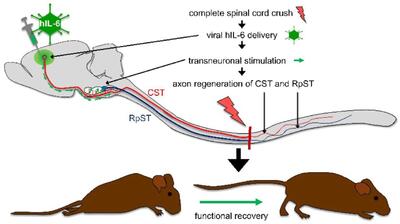

سلولهای عصبی

پرورش سلولهای مغزی در فضا راهکاری برای درمان بیماریهای عصبی

پرورش سلولهای مغز در محیط ریزگرانش فضا فواید خاصی دارد.